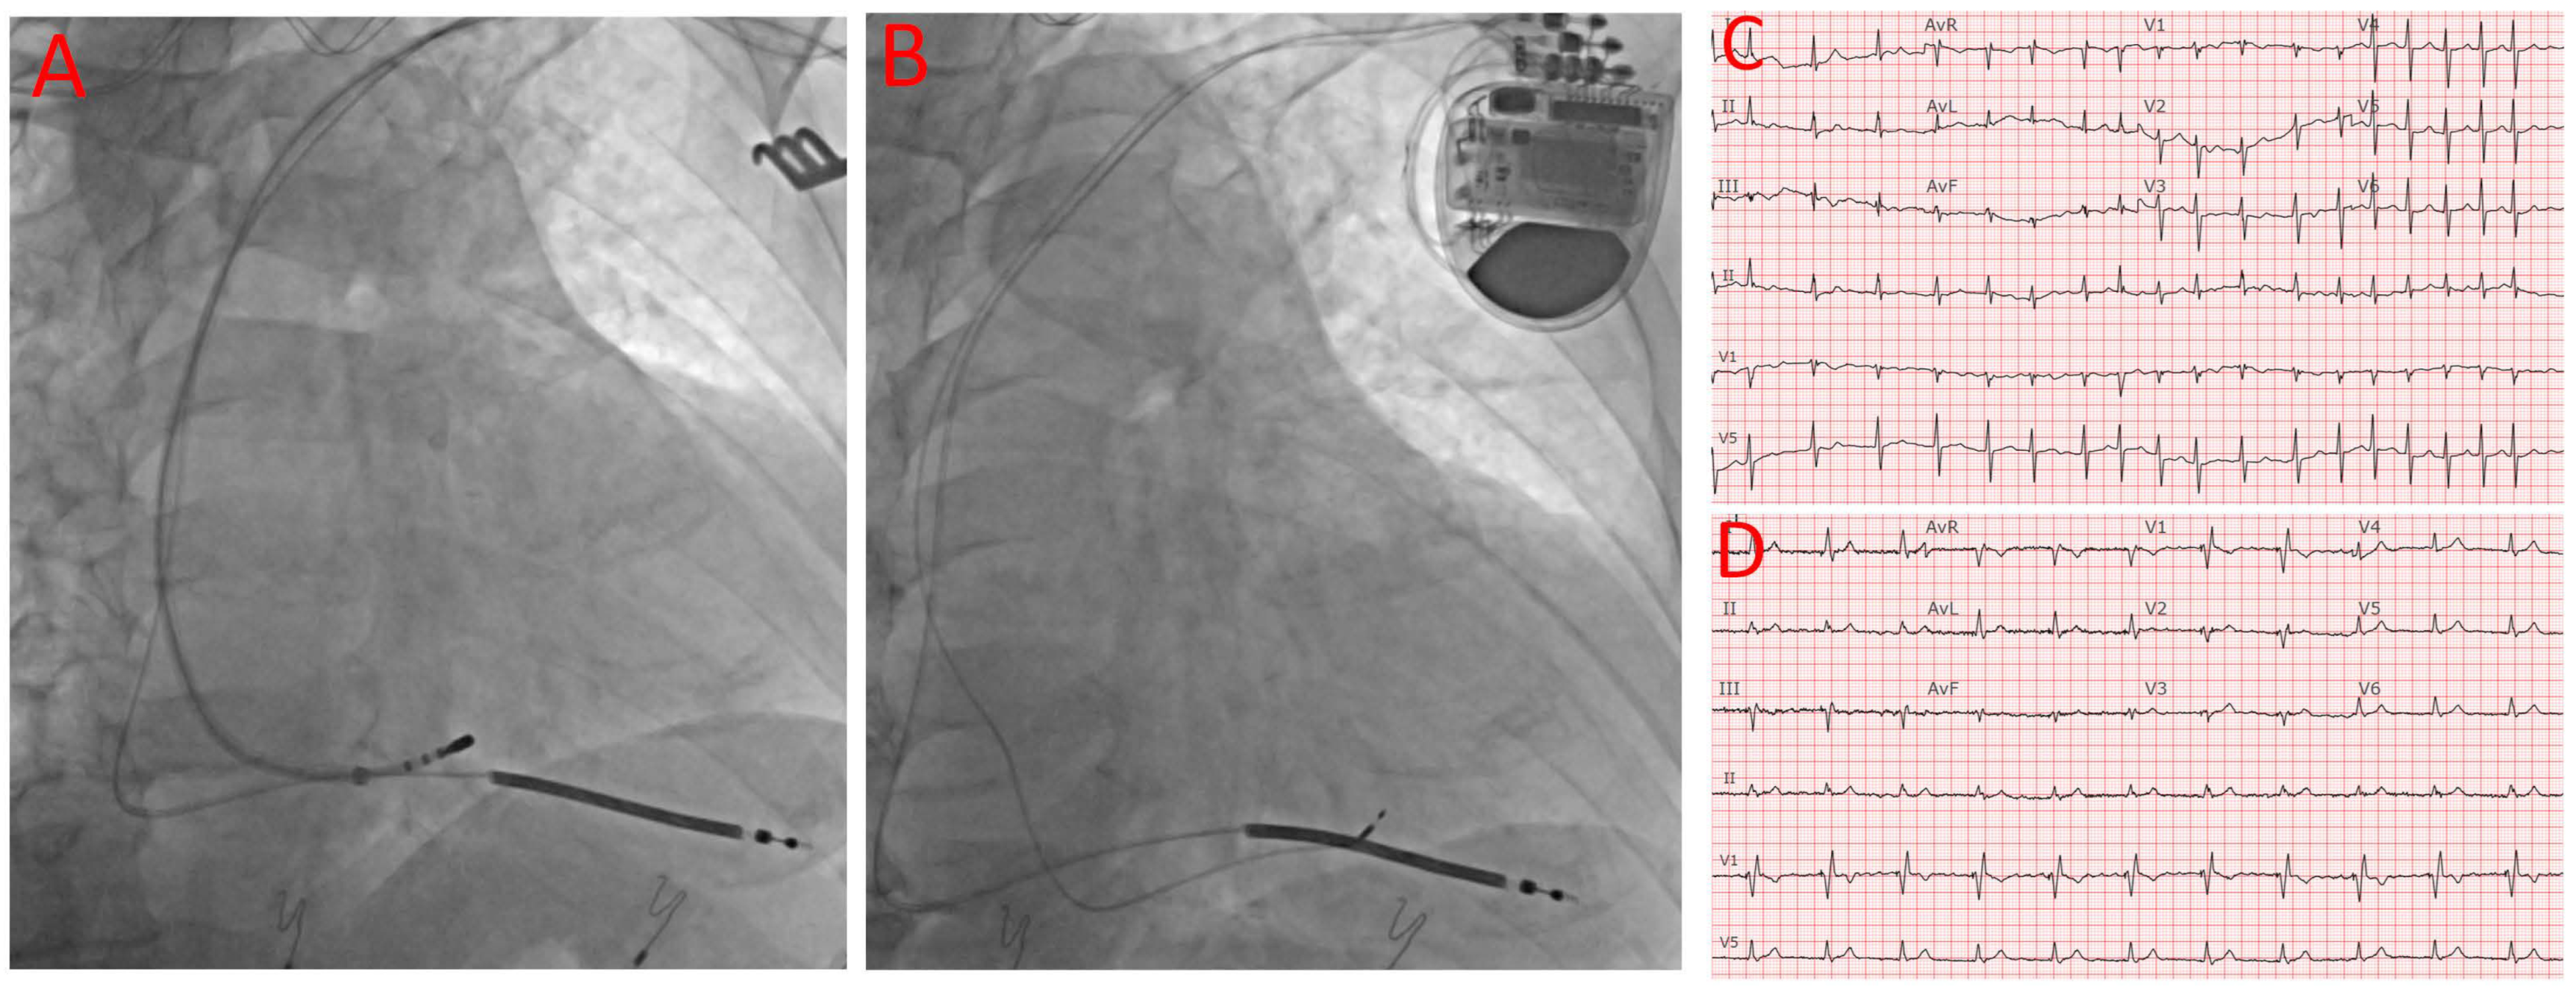

A deflectable EP mapping/ablation catheter was inserted to map the His bundle signal, and the His position was then recorded by cine imaging to facilitate AV node ablation and the subsequent implantation of the LBBAP lead. Figure 1A shows the mapping of the His position after the RV lead insertion. At this time, the device was programmed to VVI with a lower rate of 40 for backup pacing, and the ablation catheter was inserted to ablate the AV node. A standard CS delivery sheath was used to facilitate the catheter reach and to maintain stability, and a deflectable sheath would have been used if the ablation remained challenging with the standard CS delivery sheath. After achieving adequate, stable contact with the compact AV node, ablation was then initiated, typically at 50 W with a temperature upper limit of 65 degrees Celsius. After the confirmation of complete heart block, the pacing rate was typically changed to VVI 90 for the rest of the procedure. In cases where the AVN could not be successfully ablated from the superior approach, the conventional femoral approach was used after the completion of the device implant. Vascular closure devices were used to help achieve hemostasis and promote early mobilization after the procedure.

Figure 1.

Device implantation, AV node ablation, baseline ECG, and post-procedural ECG. (A) ICD RV lead position and mapping of AV node. (B) Final positions of ICD RV and LBBAP leads. (C) Baseline ECG showing AF with RVR and narrow QRS. (D) Post-procedural ECK showing LBBA pacing with narrow QRS.

The LBBAP lead implantation was then performed using the same technique as previously reported [12]. Briefly, a C315His delivery sheath (Medtronic, Minneapolis, MN, USA) was advanced into the RV over a standard J-wire. The 3830 lead (Medtronic, Minneapolis, MN, USA) was then advanced through the delivery sheath to the right ventricular septum about 1–2 cm distal to the His bundle region. Once the lead was pointed perpendicular to the septum, manual rotations were applied with forward pressure. Pacing from the 3830 lead was then performed in a unipolar fashion after every 1–2 rotations until the paced morphology demonstrated a narrow RBBB morphology indicating the capture of the LBBA. In addition to the RBBB pattern in V1, the LBBAP capture was confirmed by one of the following criteria: (1) an output-dependent transition in QRS morphology, either from non-selective left bundle branch pacing (LBBP) to selective left bundle branch pacing or from non-selective LBBP to left ventricular septal pacing (LVSP) at decremental voltage output pacing; (2) short- and stable-paced stimulus to V6 RWPT <75 ms in narrow QRS and <80 ms in an LBBB/interventricular conduction delay (IVCD); (3) V6-V1 interpeak interval > 44 ms, and (4) delay of the left bundle branch potential to V6RWPT (time to peak R wave in V6) in an intrinsic rhythm equal to the pacing stimulus of V6RWPT [13]. Based on these proposed criteria, 20 out of the 24 patients had a definite LBBP (84%), 2 out of the 24 patients likely had a LBBP (8%), 1 patient had nonselective HIS bundle pacing (4%), and 1 patient had deep septal pacing (4%). Figure 1B shows both RV and LBBAP leads are inserted. Cases that did not meet the abovementioned criteria but still had a RBBB pattern and relatively narrow QRS (<120 ms with a baseline normal QRS or <130 ms with a baseline wide QRS) were considered to be deep septal pacing.

LBBAP was successful for 22 out of the 24 patients (92% in total, 20 patients had an LBBP and two patients likely had an LBBP), followed by AVN ablation from left axillary vein access in all but three patients who required the standard right femoral approach. As shown in Table 1 for the baseline characteristics, the average age of our patients was 78 ± 5 years old. The majority were female patients (63%). All the patients presented with longstanding persistent AF with multiple comorbidities and multiple medications for either rate control or rhythm control. No RA lead was implanted considering the unlikelihood of a spontaneous conversion back to a sinus rhythm. The average pre-procedure LVEF was 44 ± 14%. Six out of the 24 patients (25%) had severely reduced LVEF values of less than 35%, and these patients underwent CRT-D implantations with an LBBAP. LBBAP instead of CS pacing was chosen for the patients with an EF < 35% because these patients did not have baseline left bundle branch blocks and CS pacing was previously not shown to improve the outcomes in patients with a narrow QRS [14,15]. Four out of the 24 patients (17%) presented with an LVEF greater than 35% but less than 50%, and these patients received an RV pacing lead, in addition to LBBAP, for cardiac resynchronization therapy. The rest of the patients (14 patients, 58%) also received RV pacing leads as backup leads in case of LBBAP failure and the potential future indication of cardiac resynchronization therapy. Overall, no significant changes in QRS duration were observed before and after the ablation, with the before-and-after-procedure QRS durations being 117 ± 32 ms vs. 123 ± 14 ms. A further analysis showed a significant reduction in a QRS duration > 20 ms in five patients (21%) who had a baseline QRS duration > 140 ms, while nine patients (37.5%) demonstrated a slightly increased QRS duration >10 ms, with a baseline QRS duration < 100 ms. Figure 1C,D shows the ECG before and after the procedure.